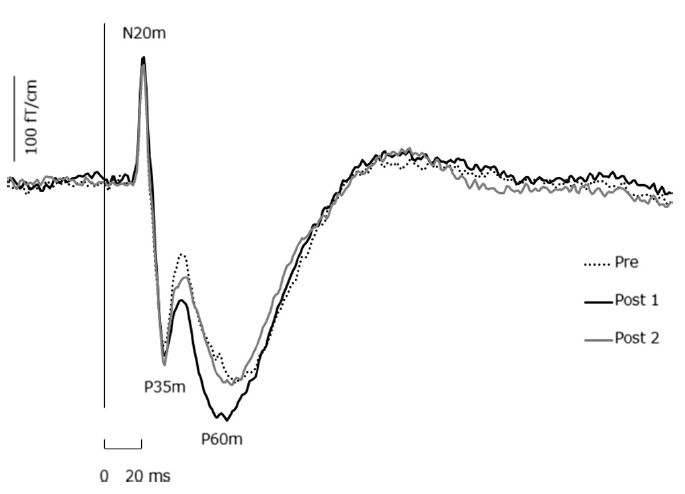

Kirimoto H, Tamaki H, Matsumoto T, Sugawara K, Suzuki M, Oyama M, Onishi H. Effect of transcranial static magnetic field stimulation over the sensorimotor cortex on somatosensory evoked potentials in humans. Brain Stim 2014 (in press)

Sugawara K, Onishi H, Yamashiro K, Kojima S, Miyaguchi S, Kirimoto H, Tsubaki A, Tamaki H, Shirozu H, Kameyama S. The effect of anodal transcranial direct current stimulation over the primary motor or somatosensory cortices on somatosensory evoked magnetic fields.Clin Neurophysiol. 2014 (in press)